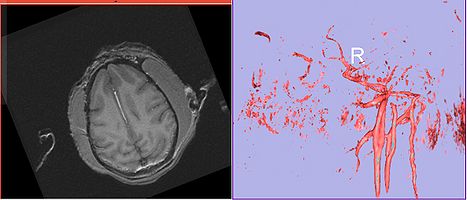

Image:calvin-angio.jpg|'''Calvin axial showing vessel and volume rendering of vasculature''' | Image:calvin-angio.jpg|'''Calvin axial showing vessel and volume rendering of vasculature''' | ||

- Angio sequence (right name?) has apparently been used for some (7 out of 10) subjects